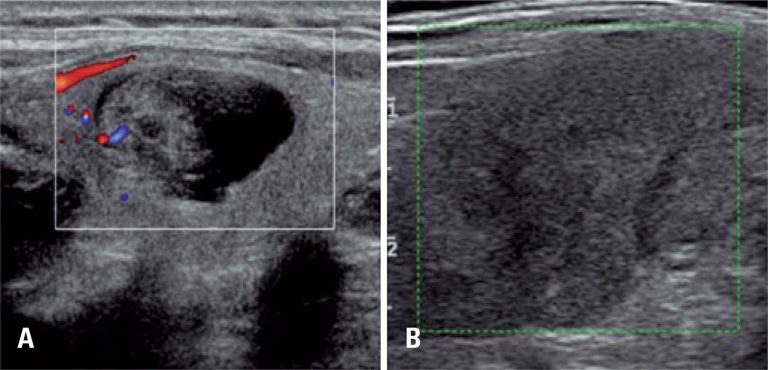

RESUMO A elastografia, procedimento difundido em ultrassonografia convencional, foi recentemente incorporada à ecoendoscopia. Trata-se de tecnologia inovadora e promissora, que visa aumentar o valor preditivo negativo da ultrassonografia endoscópica e das punções aspirativas com agulha fina. É útil para o direcionamento das punções em áreas suspeitas e, consequentemente, melhora o rendimento diagnóstico. Trata-se de técnica não invasiva, de fácil realização, sem custos adicionais ou complicações. As principais indicações são para análise de massas pancreáticas sólidas, linfonodos, lesões subepiteliais, lesões em […]

RESUMO Objetivo Apresentar a correlação entre o Thyroid Imaging Reporting and Data System (TI-RADS) e o sistema Bethesda, para relatar citopatologia em 1.000 nódulos tireoidianos. Métodos Estudo retrospectivo realizado no período de novembro de 2011 a fevereiro de 2014, que avaliou 1.000 nódulos tireoidianos de 906 pacientes submetidos a exame de ultrassonografia e à punção aspirativa por agulha fina. Resultados Observou-se associação significativa entre o TI-RADS e o resultado da classificação de Bethesda (p